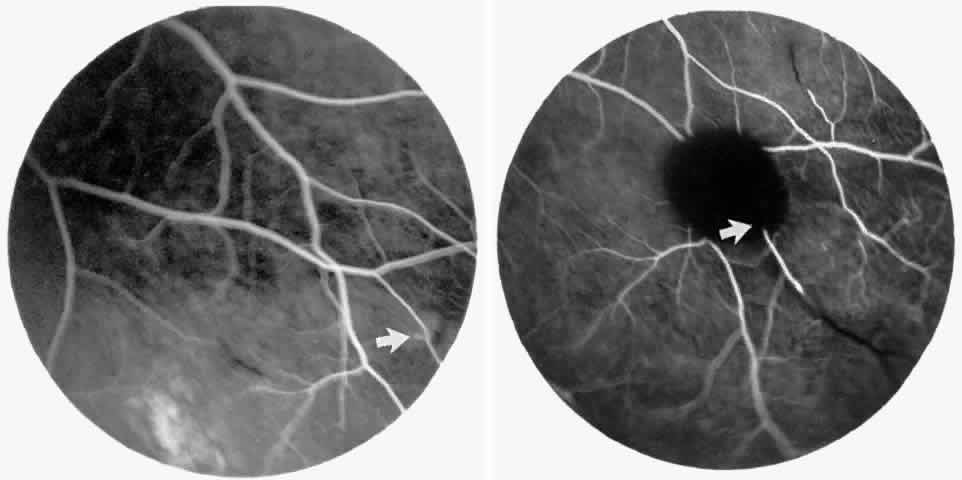

Macular Small Vessel Occlusions

Occlusions of the fine vasculature of the macular and perimacular area have been reported in 10% to 40% of patients with sickle cell disease.18,83,91–99 In the acute phase, the occluded vessel will have a dark red appearance and may appear as a dark line on fluorescein angiography (Fig. 9). Nerve fiber layer infarcts (cotton-wool spots) are seen (see Fig. 8D and E;Fig. 10).100

Fig. 9. A 27-year-old man with homozygous sickle cell anemia. A. Fluorescein angiogram of the right eye shows multiple arteriolar occlusions temporal to the fovea (arrows). B. Same area 6 months later shows more extensive occlusions. The black arrowheads (A and B) identify corresponding arteriolar bifurcation.

Fig. 10. A 33-year-old woman with SC disease and stage III sickle cell retinopathy. A. Photograph of the right eye shows a cotton-wool spot with a dark segment identifying the occluded vessel (arrow). B. Fluorescein angiogram demonstrates nonfilling of the occluded vessel (arrow). C. Eighteen months later, the occluded vessel is still visible (arrow). D. Fluorescein angiogram demonstrates that there is still nonfilling of the vessel (arrow).